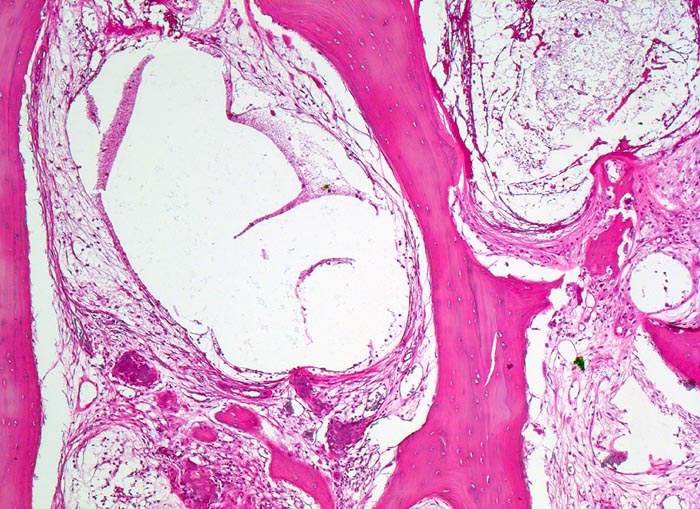

Makroskopisch ist die Nekrose im Anfangsstadium durch eine intensiv gelbe Verfärbung mit hämorrhagischem Randsaum charakterisiert. Häufig kommt es zur flächenhaften Ablösung des ansonsten intakten Gelenkknorpels (DD Arthrose!) zwischen subchondraler Knochenlamelle und angrenzender Spongiosa. In den Spätstadien sind die Nekrosezonen grau-gelb gefärbt und von körniger Konsistenz. Ein Teil der nekrotischen Spongiosabälkchen dient als Leitschiene für die Neubildung von Osteoid und mineralisierten Trabekeln, die an der Aussenseite angelagert werden. In der Nekrosezone kommt es zur Sequestrierung von Knochenbälkchen durch Frakturen. Die Markräume werden bindegewebig organisiert. In der Peripherie besteht initial ein hyperämischer Randsaum und im Verlauf kommt es zur Ausbildung einer metaplastischen Knorpel- und Knochenneubildung mit Randsklerose. Das Endstadium der Abräumreaktion untergegangener Knochenabschnitte stellt eine meist subchondral lokalisierte pseudozystische Umwandlung dar. Schliesslich kollabiert der Femurkopf und der Verlust der Gelenkkongruenz führt zu einer fortschreitenden sekundären Coxarthrose (> 3192)

• Flächenhafte Ablösung des gut erhaltenen Gelenkknorpels zwischen subchondraler Knochenlamelle und angrenzender nekrotischer Spongiosa.

• Pseudozystische Hohlräume in den nekrotischen Markräumen.